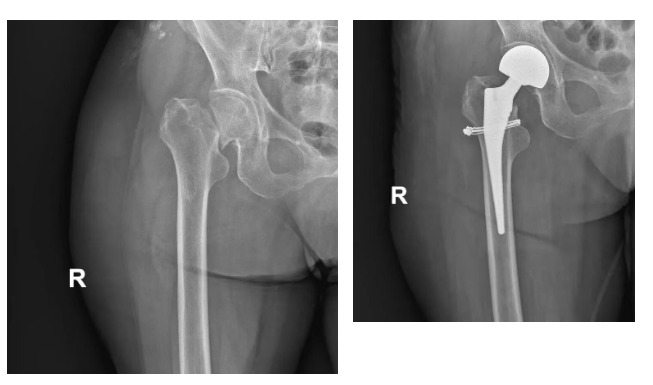

據(jù)了解,前段時間,該患者在家中不慎跌倒,右髖疼痛,不能行走,急忙來醫(yī)院急診科就診,急診右髖關節(jié)正位示:右側股骨頸骨折,隨后收入醫(yī)院骨科?!霸?3年的時候,因為腰椎骨折,在鴻港醫(yī)院做的經(jīng)皮椎體成形術,后來恢復特別好,這次摔傷后,我們也是第一時間選擇了咱們醫(yī)院!”患者家屬說道。

入院后,由于患者患有心臟房顫,雙下肢靜脈血栓等疾病,病情復雜,骨科副主任、副主任醫(yī)師徐紅立帶領團隊制定手術方案,在患者病情穩(wěn)定且各項檢查無明顯手術禁忌癥后,第一時間安排了骨折手術,成功為患者實施了“右側人工股骨頭置換術”,術后經(jīng)過精心對癥治療,患者病情穩(wěn)定后順利出院。

然而,命運多舛,該患者出院后沒過多久,在家中不小心再次跌倒,家屬連忙找到徐紅立副主任,來院拍片診斷為股骨假體周圍骨折,骨折的位置非常特殊——就發(fā)生在剛置換的右側人工股骨頭假體周圍,屬于臨床上處理難度較大的“假體周圍骨折”。